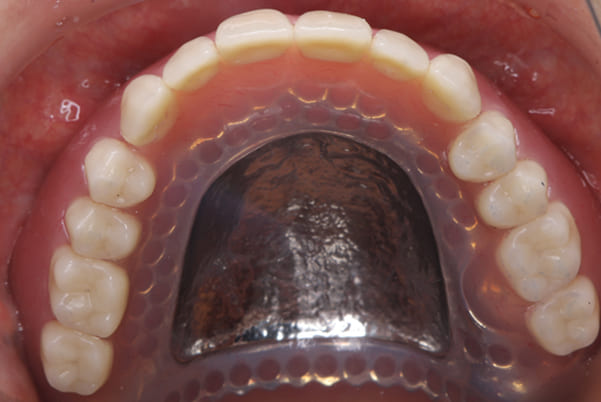

上顎治療後

根のみの7本は虫歯にもなっており歯肉は腫れあがっています。

残りの歯もレントゲンで重度の歯周炎によりぐらぐらな状態でした。

精密な型どりは、通常保険治療では使用しない、この患者様だけに合った型を取るトレーを作製、また寸法変化の最も少ない精密なシリコンを用いてお口の中を精密に限りなく再現する型どりの方法で型をお取りしました。

完成前に適合や見た目のチェックでは、咬む力で義歯がたわみ、残りの歯に負担がかからないよう、見えない内側は、金属を用い、強度を増し、また金属のため薄くすることで違和感をなくす設計とし、完成前に試し合わせを行い、装着感、審美性を確認しました。